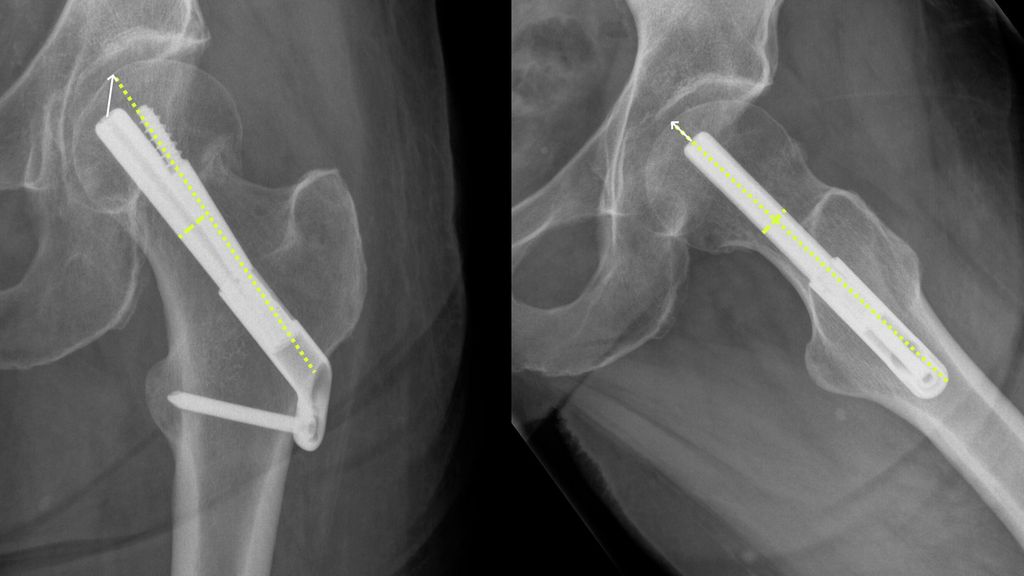

Die Indikationsstellung zur Schenkelhalsosteosynthese erfolgte in 49 Fällen (58,3%) bei Frakturen der Kategorie Garden I. 33 Patient:innen (39,3%) wiesen eine nicht dislozierte Fraktur auf (Garden II). In jeweils einem Fall wurde eine Osteosynthese bei höhergradiger Dislokation im Rahmen eines palliativen Settings unternommen (Garden III: n=1, Garden IV: n=1). Über das gesamte Kollektiv zeigte sich ein Tip-Apex-Abstand (Abb. 3) von 2,12 (±0,63)cm im Mittel. Das radiologische Merkmal war kein Prädiktor für eine Revision (p=0,427).